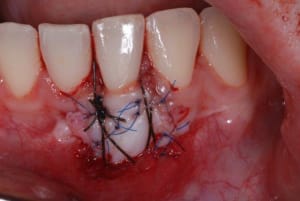

2010-09-30_001_naradp.jpg